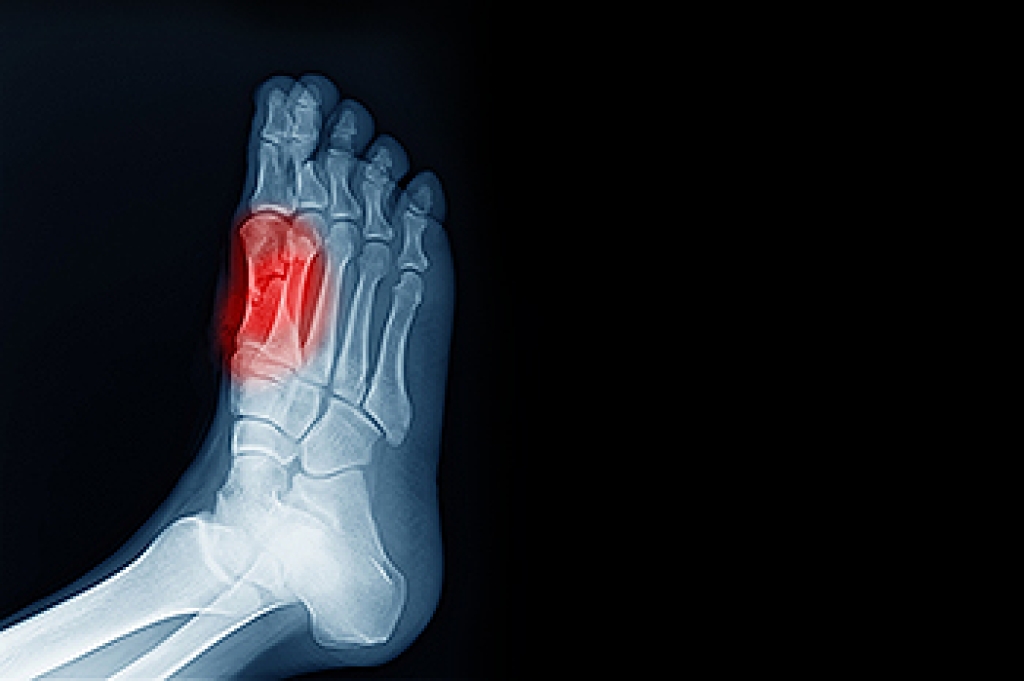

In order to diagnose your bunion, your podiatrist may ask about your medical history, symptoms, and general health. Your doctor might also order an x-ray to take a closer look at your feet. Nonsurgical treatment options include orthotics, padding, icing, changes in footwear, and medication. If nonsurgical treatments don’t alleviate your bunion pain, surgery may be necessary.